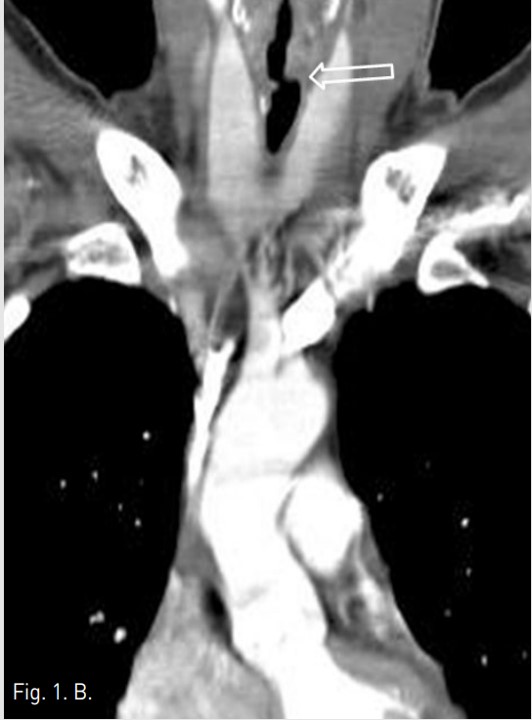

Fig. 1. B

Fig. 1A-1B Axial chest CT image (A) shows tracheal stenosis(Arrow in A) at thyroid gland level. Coronal chest CT image (B) shows multifocal irregular luminal narrowing (Open arrows in B) of upper trachea from C6 to T1 level.